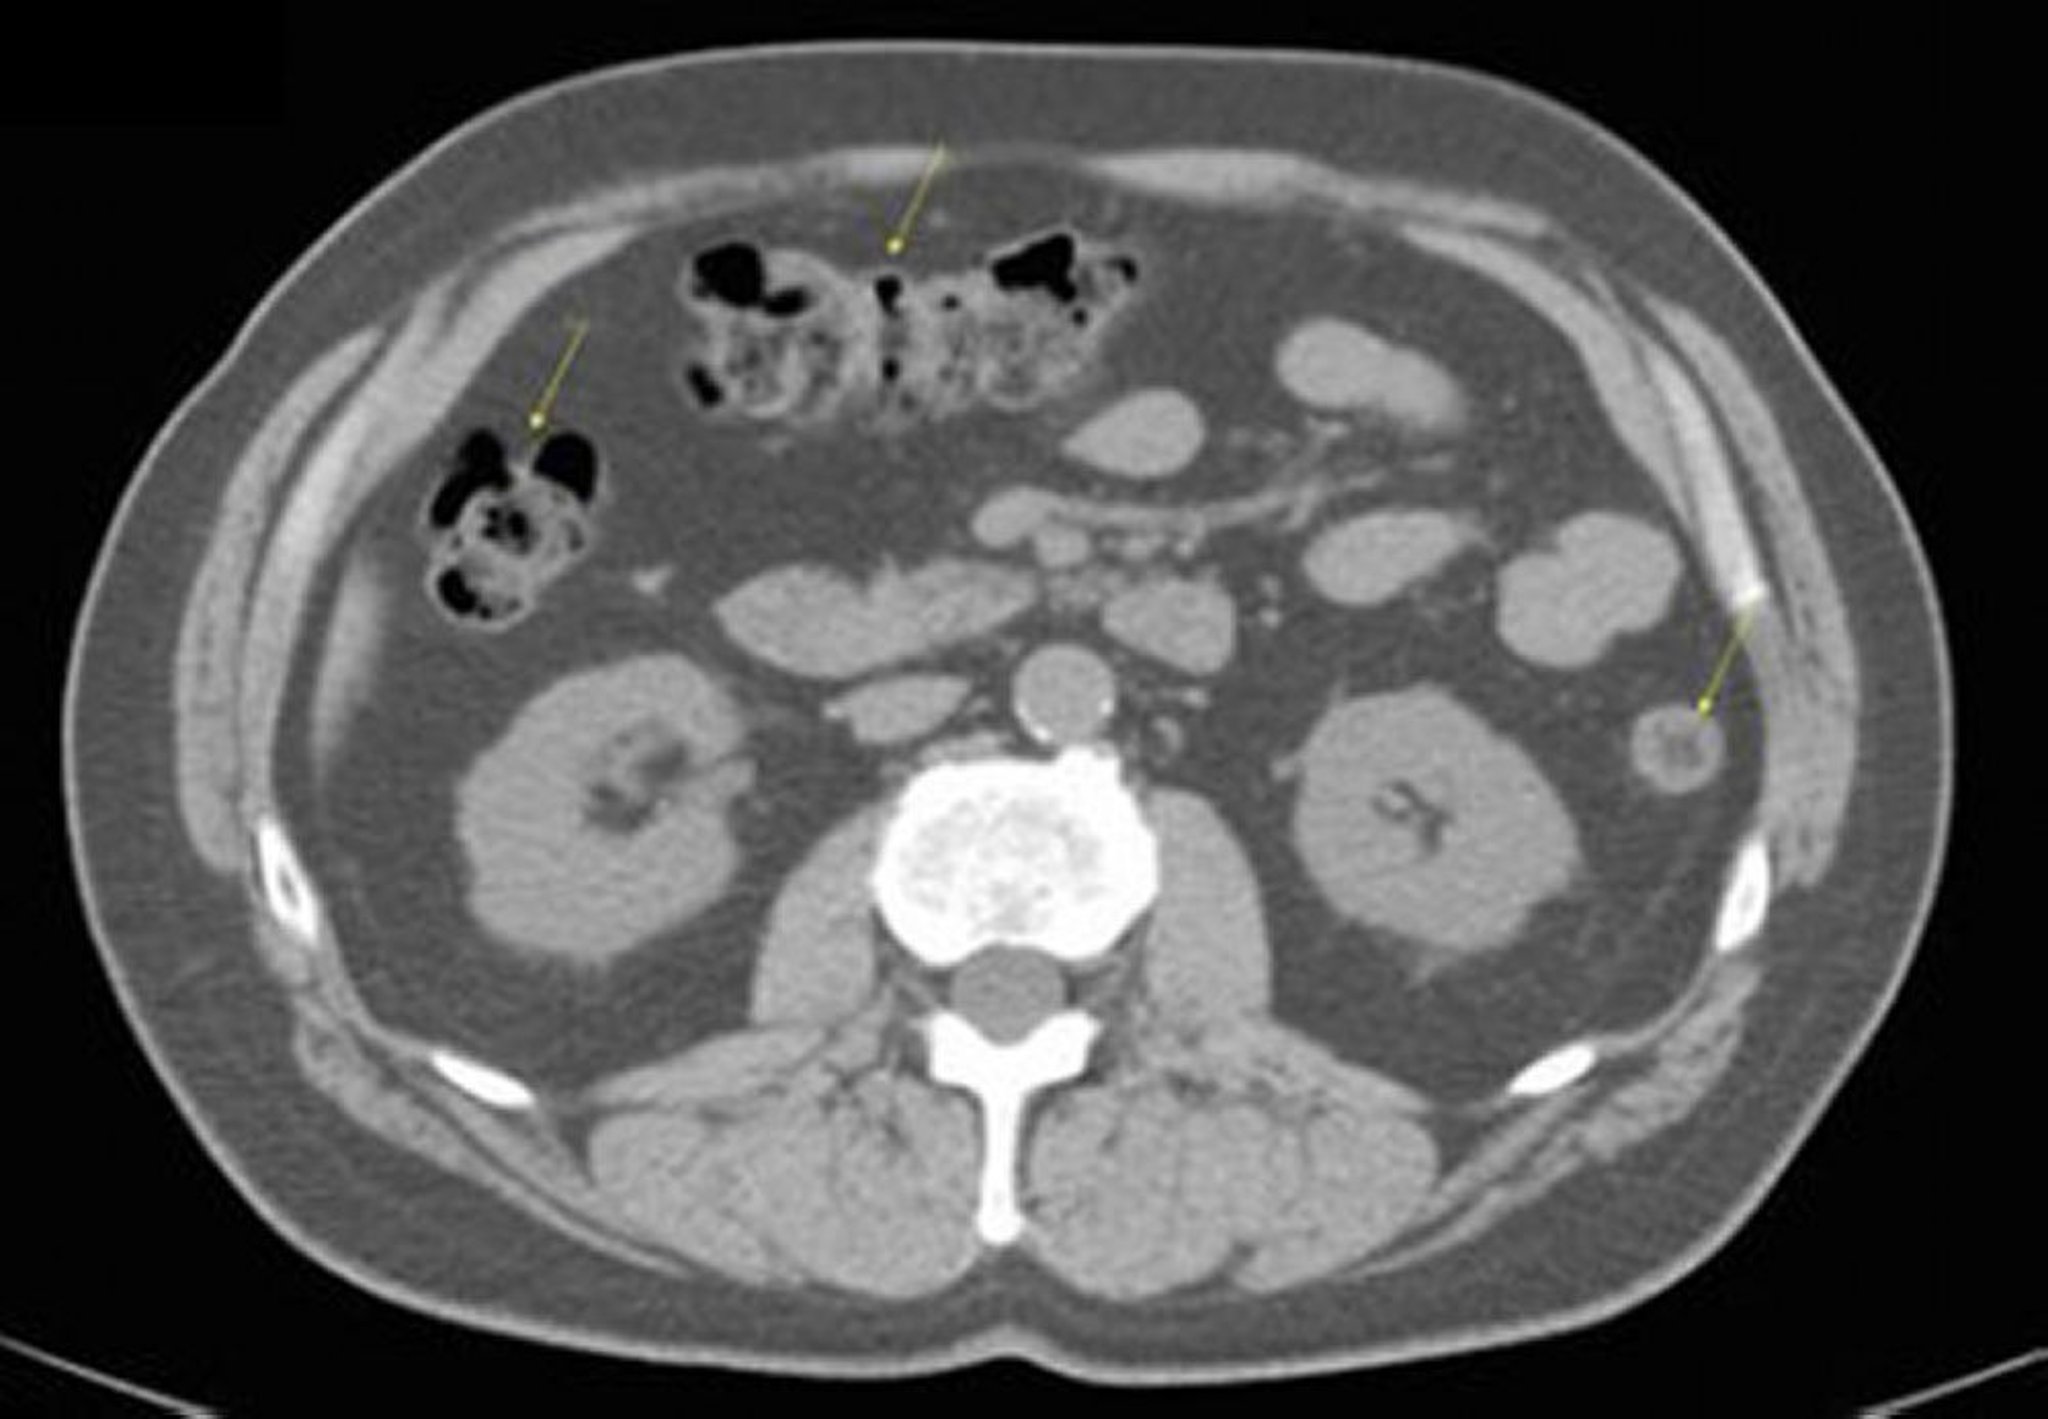

TC senza contrasto dell'addome e della pelvi che mostra un'anatomia normale (Slide 17)

Questa immagine mostra il colon (frecce).